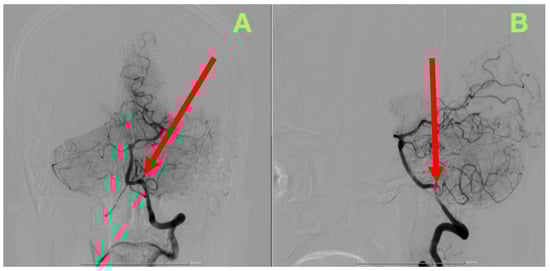

2. Case Presentation